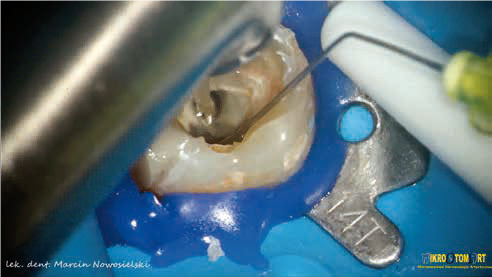

ARTYKUŁ Z FILMEM: Opis przypadku leczenia kanałowego zęba 37 z przewlekłym stanem zapalnym tkanek okołowierzchołkowych przy użyciu laserów Er:YAG i Nd:YAG oraz ponownego leczenia kanałowego zęba 36 z usunięciem złamanych narzędzi

Opis przypadku leczenia kanałowego zęba 37 oraz ponownego leczenia kanałowego zęba 36 z usunięciem złamanych narzędzi, z rozległym, przewlekłym zapaleniem tkanek okołowierzchołkowych z użyciem lasera Er:YAG (2940 nm) do wspomożenia procesu aktywacji roztworów płuczących oraz lasera Nd:YAG (1064 nm) w celu dezynfekcji głębszych struktur zębinowych, wraz z rekonstrukcją korony jako przygotowanie do dalszego leczenia protetycznego. W leczeniu zęba 37 zastosowano zachowawcze podejście do usuwania twardych tkanek zęba (tak zwane Truss Access), którego bezpieczne i przewidywalne wykorzystanie uwarunkowane było zastosowaniem lasera Er:YAG podczas procedur płukania komory i systemu kanałowego. Zastosowanie powyższego urządzenia pomogło i znacząco przyspieszyło proces usunięcia złamanych narzędzi z zęba 36 dzięki wykorzystaniu tak zwanej fali uderzeniowej (shockwave) wywołanej przez efekt fotoakustyczny (photon induced photoacoustic streaming).

Description of the case of root canal treatment of tooth 37 and re-treatment of tooth 36 with the removal of broken instruments, with extensive, chronic inflammation of the periapical tissues with the use of the Er:YAG laser (2940 nm) to support the activation process of rinsing solutions and the Nd: YAG laser (1064 nm) to disinfect the deeper ones dentin structures, along with the reconstruction of crown structures as a preparation for further prosthetic treatment. In the treatment of tooth 37, a conservative approach to the removal of hard tooth tissues (the so-called Truss Access) was used, the safe and predictable use of which was conditioned by the use of the Er:YAG laser during the rinsing procedures of the chamber and the canal system. The use of the above device helped and significantly accelerated the process of removing broken tools from tooth 36 thanks to the use of the so-called Photon induced photoacoustic streaming.